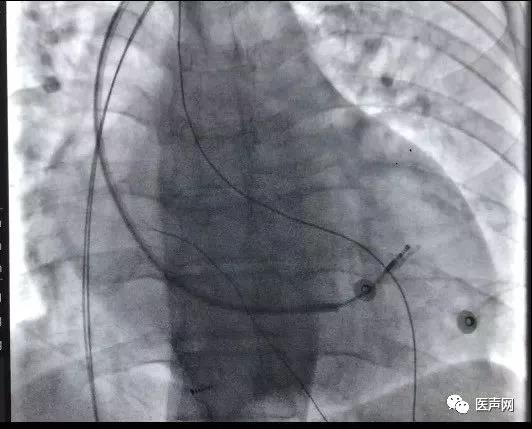

沿导丝送入可撕开长鞘至左室,送入导线(2088TC 65cm)至三维标测指定的靶向位点,经测试,阈值0.5V,螺旋固定。

常规植入右房右室导线,连接机器,手术结束。